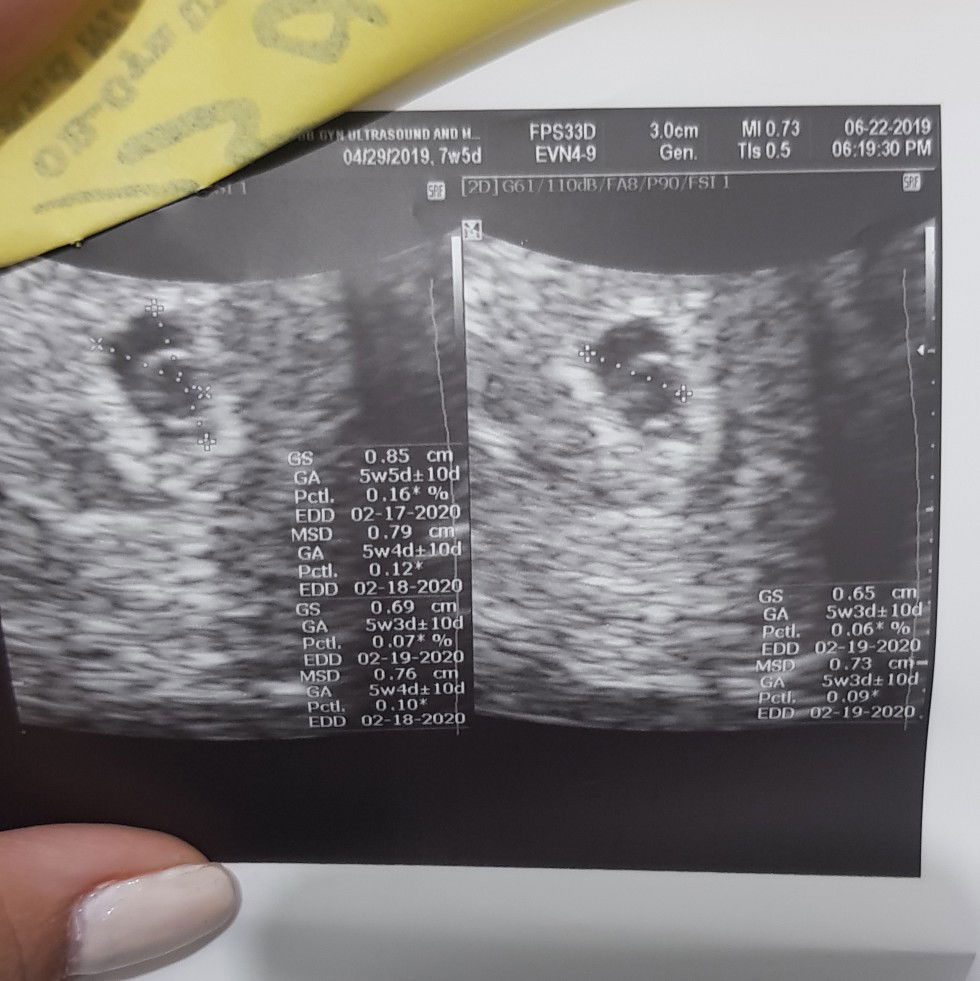

Hi Mommies. Share ko lang story ko. Medyo mahaba po. This is my short adventure with my baby (now an Angel) June 6: my first PT showed 2 lines. Hindi pa ko naconvinced nun kase faint yung 2nd line. Nag 2nd PT ako nung hapon when I woke up (night shift ako) and 2 lines ulit. June 10 (morning): nag PT ulit ako, third time, and 2 lines ulit. June 10 (afternoon): nagpa transV ako and lumabas na I was positive pregnant and gestational sac palang ang nakita saken, GA was 7 weeks based on my last day of mens. Meron din nakitang subchorionic bleeding kaya niresetahan ako ng progesterone and folic acid. June 11-22: I was taking my meds religously and made sure that I eat healthy enough. Naka experience din ako ng madalas mag CR and soreness ng breast and other symptoms of early pregnancy. June 22: Nagpa transV ulit ako kase I wanted to know if may heartbeat na si Baby. And yes!! 120 bpm ni Baby, 5weeks and 5days na sya based sa measurement nya. Super happy ko nung nakita ko ung heart nya na pumipintig sa monitor habang inu-ultrasound ako. Sobrang cute nya. However, nalaman din na nasa case na Oligohydramnios sya, meaning maliit ang sac for the baby and kulang sa amniotic fluid. I was asked to drink a lot of water (which I surely did). And dahil sa ibang clinic ako nagpa ultrasound, hindi ako narisetahan ng pampakapit. I had to wait for monday dahil un ang sched ng OB ko. Throughout this day, I was feeling fine and okay kami ni Baby. Sobrang saya namin parehas ni hubby kse nga nakita namin na buhay na si baby and anjan na sya. June 23 (morning): i felt a small pain sa puson which dinedma ko lang kse medyo nakakaramdam din ako ng ganun nung mga nakaraang araw. Also, biggest milestone namin today kase nasabi ko na sa parents ko and they were so happy and excited for baby!! Super saya ulit namin ? June 23 (rest of the day): hindi nawala ung sakit ng puson ko then I was also spotting. Medyo nag worry na ko pero bawal mastress so pinahinga ko nalang. June 24 (morning): I was awaken by the pain in my belly. As in super sakit ng puson ko, parang dysmenorrhea na ung pain. Also may spotting padin and mas dumami. Despite of this pain, I still managed to went to my OB for my follow up check up. Nag-ie din ako since ininform ko sya about my bleeding then she confirmed na I was bleeding nga. She also read the findings of my ultrasound and nag reseta ng pampakapit and vitamins. By this time, sobrang sakit na ng puson ko. Feeling may mens na talaga. June 24 (afternoon): pagkauwi galing hospital, nag lunch ako and uminom agad ng gamot. I was so thankful to my mom kse sya ang sumama saken and bumili ng meds ko. Super alaga din sya saken. I was feeling worse as well kase lalong sumasakit yung puson ko and lalo ako nag bbleed. I just kept praying and drinking water. Umasa ako na makakatulog ung pampakapit. June 24 (6pm-8pm): i tried to sleep early pero nagigising ako in the middle of my sleep dahil sa sobrang sakit ng puson ko. I also took my med for the night after my early dinner. June 24 (10pm): Sobrang sakit na ng contractions ko, bleeding was worst and kahit sa ihi ko may blood na. I was so nervous by that time pero I have to avoid stress kase baka lalo lumala condition namin ni baby. I couldn't sleep na rin due to the pain. My mom told me na mukha daw akong nag-lalabor kse yung sakit is mawawala for a while then babalik nanaman. As in parang nag lalabor talaga. We we're also discussing if dadalhin na ko sa hospital or if kaya ko ba til the next day pra mapa ultrasound ako to check if my baby is okay or not. June 25 (1am): I went to pee and that's when the time I felt na may nalaglag na buong dugo from my vagina, I was crying already kahit d ko pa nakikita then I looked, yes it's my baby :( all those pain pala was really contractions because he/she is going out. I cried so hard I cant even remember the details of how things went. Nagkaulirat nalang ulit ako nung nasa hospital na ko to have my ultrasound. June 25 (2am): ultrasound result shows no sign of baby :( kahit alam ko na beforehand, mas masakit parin marinig. Iyak lang ako ng iyak sa buong madaling araw. Sobrang lungkot dahil somehow kumapit na ko sa idea na buhay si baby dahil may heartbeat pero natalo kami sa complications nya :( June 25 (8am): I had D&C... It was a very short adventure. When I woke up after my operation, namiss ko bigla si baby. I lost him/her @ 1.5months. Yes it was too early but he/she was my first baby, my first miracle, my truest love. When I recall all that had happened, I would still cry hanggang sa parang naubusan na ko ng luha. It was all painful, so painful. Prayer, acceptance and time will heal us ?